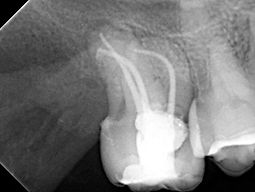

Fotos